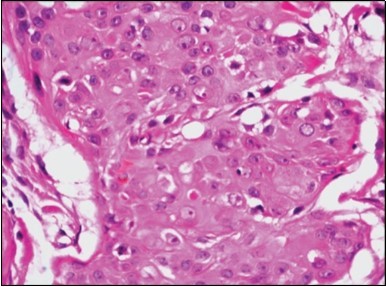

Granular arrangement of malignant cells and intercellular bridges are conspicuous with the demonstration of nuclear atypia, pleomorphism, prominent mitosis and tumour necrosis. A peripheral palisade is discernible within the cellular aggregates. Mitotic figures are common and can be quantified as up to 12 mitosis/ high power field. Tumour differentiation can prominently be of the ductal category with the demonstration of intra-cytoplasmic lumina. Comedo type tumour necrosis is evident along with foci of squamous differentiation The neoplasm is reactive to periodic acid Schiff ‘s (PAS) stain. (Figure 1, Figure 2, Figure 3, Figure 4, Figure 5, Figure 6, Figure 7, Figure 8, Figure 9, Figure 10, Figure 11, Figure 12, Figure 13.

Figure 4.Cellular atypia, mitosis and focal necrosis in eccrine porocarcinoma(16).

Classically, intra-epidermal and dermal nests of tumour cells exhibiting cellular atypia and enhanced mitotic activity are enunciated. Tumour aggregates articulate well demarcated, enlarged, atypical polygonal cells with indistinct cellular and nuclear outline, nuclear hyperchromasia , irregular nuclei, vesicular or prominent nucleoli and minimal eosinophilic cytoplasm. Polygonal tumour cells can depict central keratinisation 6, 7.